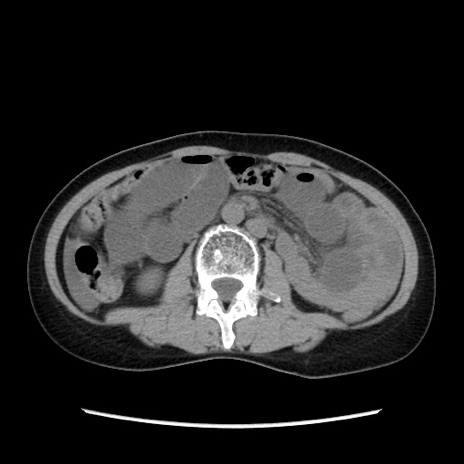

症例32(横断像)

【症例】40歳代 女性

【主訴】上腹部痛、嘔気・嘔吐

【現病歴】約9時間前頃から急に上腹部痛、嘔気、嘔吐が出現。改善しないため救急要請。

【既往歴】子宮頚癌(広汎子宮全摘術、放射線療法)、腸閉塞

【身体所見】腹部:平坦、軟、腸雑音亢進、上腹部を中心に腹部全体に圧痛あり。

【データ】WBC 8400、CRP 0.03